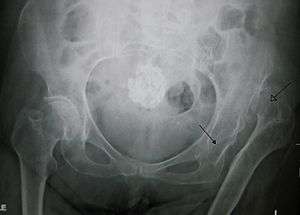

Dislocation of the hip is a common injury to the hip joint. Dislocation occurs when the ball–shaped head of the femur comes out of the cup–shaped acetabulum set in the pelvis. This may happen to a varying degree. A dislocated hip, much more common in females than in males, is a condition that can either be congenital or acquired.[1] Understanding the epidemiology, anatomy, difference between congenital and acquired, screening, treatments, and rehabilitation are all relevant to the topic.

The hip joint includes the articulation of the femoral head (of femur) and the acetabulum of the pelvis. In hip dislocation, the femoral head is dislodged from this socket. Posterior dislocation is the most prevalent, in which the femoral head lies posterior and superior to the acetabulum. This is most common when the femur is adducted and internally rotated. The opposite is true for the shoulder, where the most common dislocation occurs in the anterior and inferior directions.[1] The posterior side of the hip exhibits primarily hip extension, dealing with the muscles: gluteus maximus, hamstring muscles (biceps femoris, semitendinosus, semimembranosus), and the six deep external rotators (piriformis, obturator externus, obturator internus, gemellus superior, gemellus inferior, and quadrates femoris).[4]

Nine out of ten hip dislocations are posterior. The affected limb will be shortened and internally rotated in this case. Posterior dislocations with an associated fracture are categorised by the Thompson and Epstein classification system.